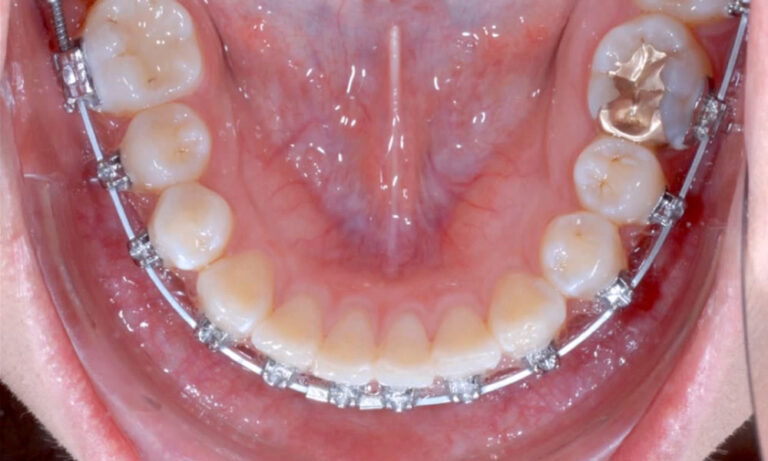

Lower Impacted (Orthodontics)